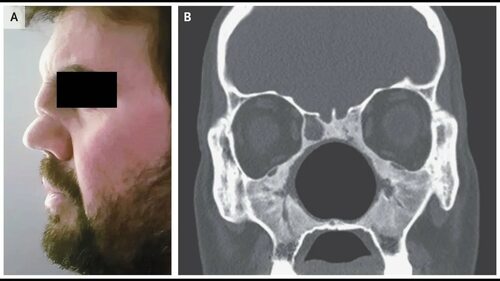

В этой статье представлены фотографии, связанные с болезнью Вегенера. Болезнь Вегенера, также известная как пироплазмоз, является инфекционным заболеванием, передающимся через укусы клещей.

Основными симптомами болезни Вегенера являются высыпания на коже, повышение температуры тела, слабость и усталость. На фотографиях можно увидеть типичные высыпания на коже и их распределение по телу.